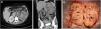

Pielonefritis xantogranulomatosa

Xanthogranulomatous pyelonephritis